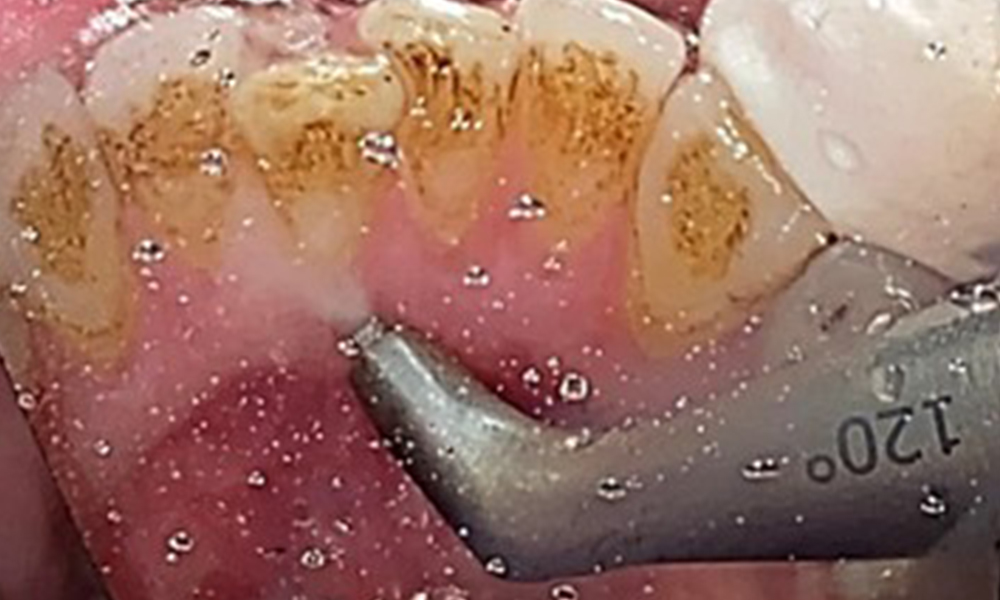

Instruction and motivation are important components of these appointments. Good home-based intraoral hygiene behaviour and understanding are important for patients. Plaque accumulation is particularly evident in the cervical regions (Fig. 8).

These must be discussed with the patient, and improvements to the teeth-brushing technique must be practised. A soft toothbrush attachment is recommended for home-based intraoral hygiene due to the presence of erosions and attritions.

The objective would be to control disease risk by removing supragingival and subgingival biofilm. The instruments can be selected based on patient needs. First, calculus and any concretions must be removed using ultrasonic and/or manual instruments (Fig. 10).